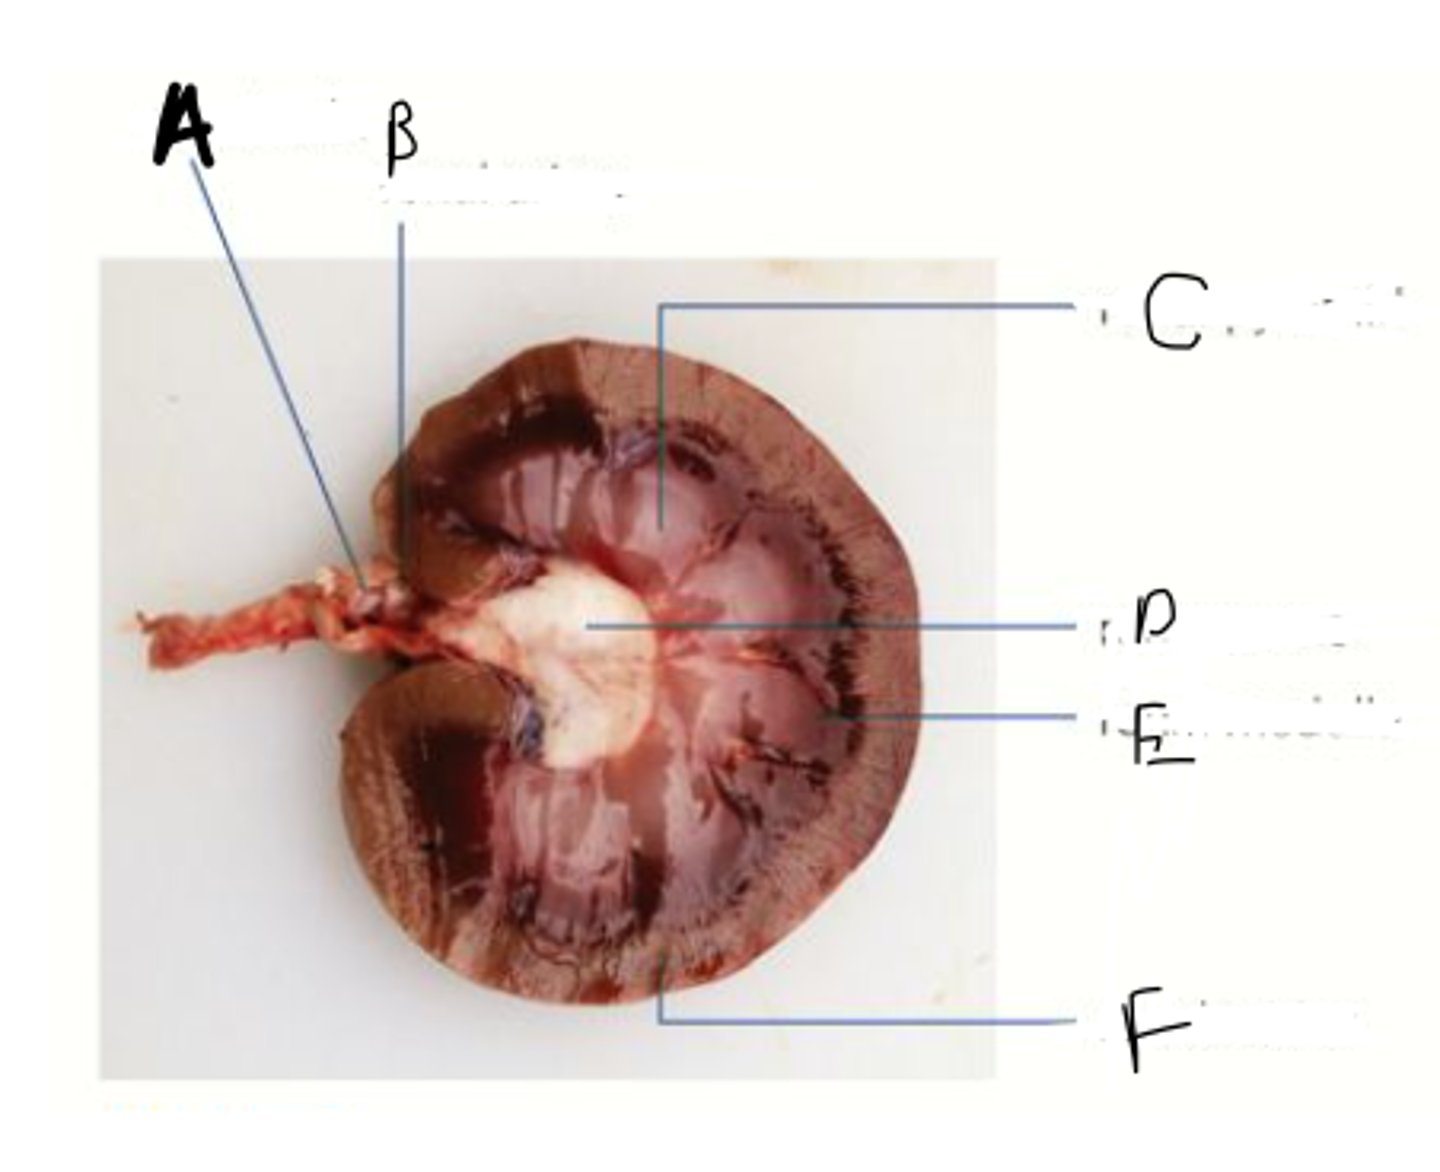

name A-F

A - renal vein

B - renal artery

C - renal pyramid

D - renal pelvis

E - renal medulla

F - renal cortex